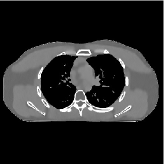

For a 3D cone-beam CT problem, circulant preconditioning is less accurate because the matrix is inherently shift-variant due to the system geometry and/or spatial variations in detector response [44]. Despite this fact, we select a circulant preconditioner to approximate in (4), and solve (2) in 3D CT reconstruction using more PCG inner iterations. The reason is three fold. First, a circulant preconditioner is still one of the classical options to approximate a shift-variant matrix (e.g., ) and accelerate CG (see, for example, [44, 45]). Second, effective learned transforms are generally close to orthogonal (the same applies to the 2D case), and a scaled identity preconditioner can approximate the term . Third, a few PCG iterations in Algorithm 1 can provide fast convergence: 1) Fig. 2 shows that and PCG iterations give very similar convergence rates; 2) in the 3D CT reconstruction, the convergence rates of Algorithm 1 are comparable to those provided in 2D CT reconstruction – see Fig. 5. More sophisticated preconditioners might provide faster convergence [46, 47].

III-B2 Algorithm Convergence Rate

Our main concern in convergence rates of Algorithm 1 lies with an inaccurate preconditioner (e.g., circulant one) particularly for the 3D sparse-view CT reconstructions. To see the effects of using a loose preconditioner in Algorithm 1, we compared the convergence rates of the 3D case with those of 2D (Fig. 5(a) and Fig. 5(b)). In the first iterations, Algorithm 1 converges faster in 2D experiments than 3D experiments. However, after iterations, the convergence rates of Algorithm 1 are similar in both 2D and 3D reconstructions. In addition, more PCG (with a circulant preconditioner) iterations does not significantly accelerate Algorithm 1 (see Fig 2). These empirically observations imply that, in the 3D sparse-view CT reconstructions, Algorithm 1 using a circulant preconditioner ( PCG iterations) is a reasonable choice.